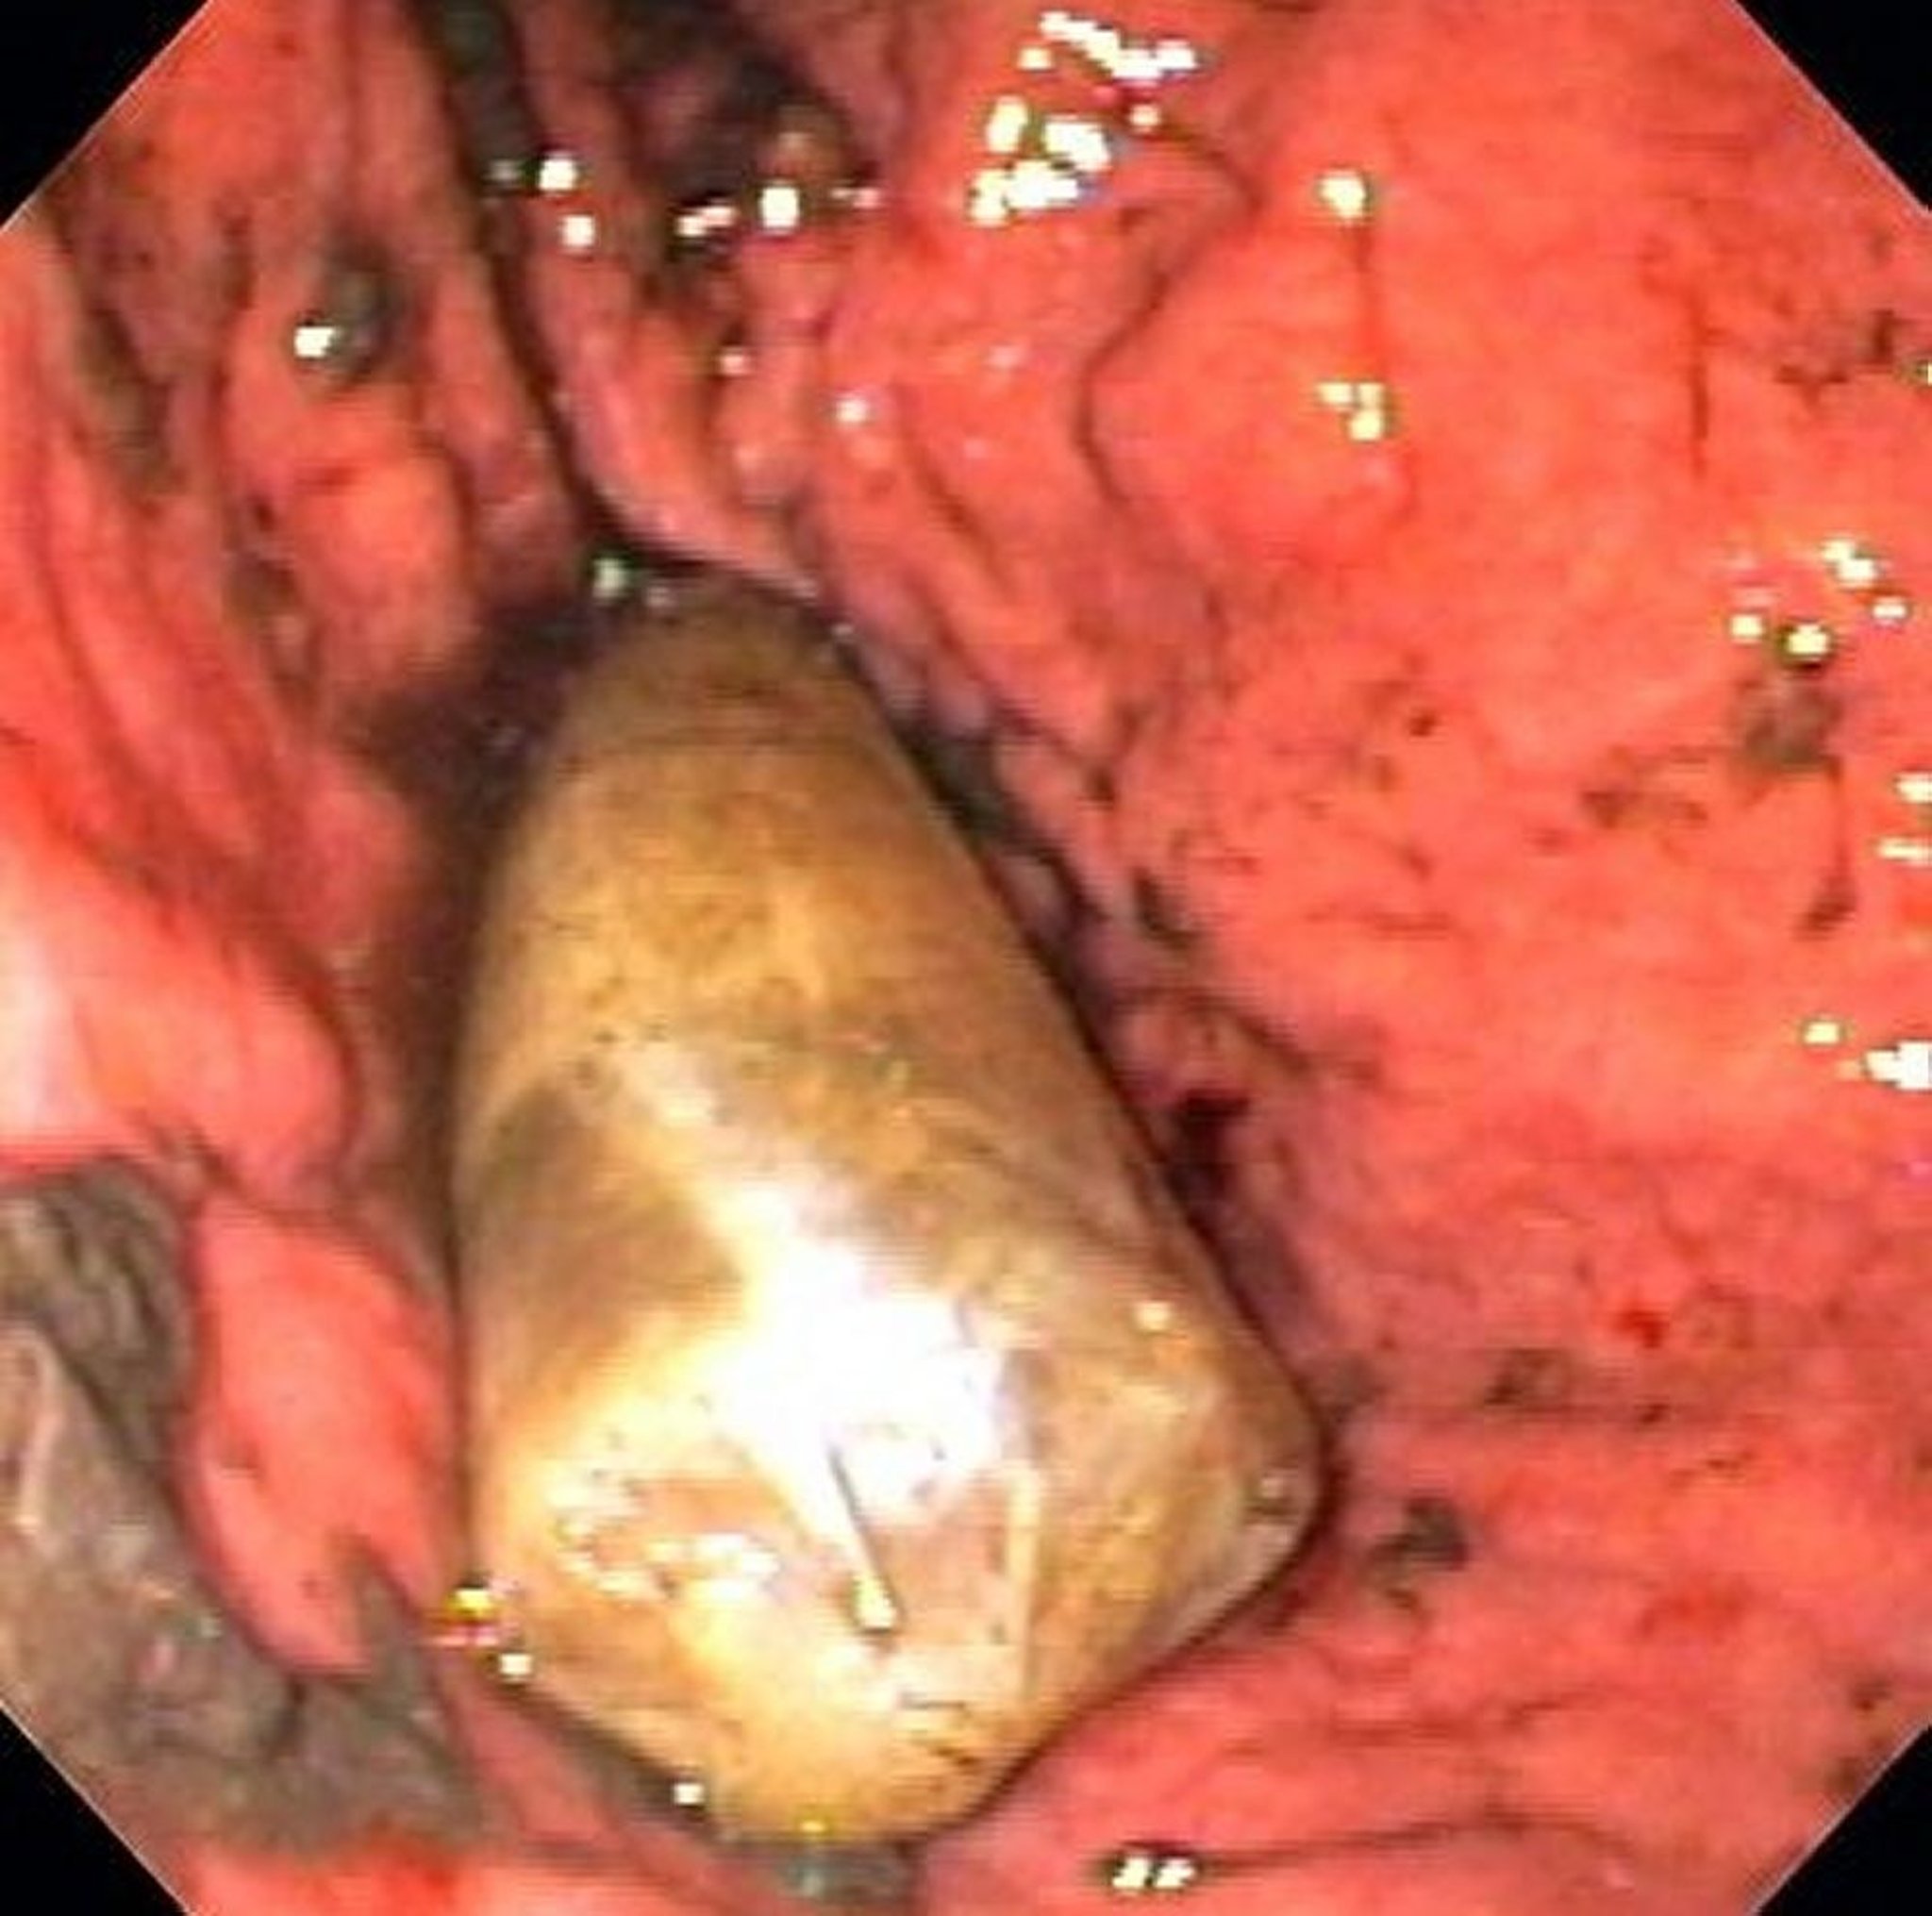

جسم أجنبي في المعدة (تنظير داخلي)

تُظهر هذه الصورة علبة دواء في داخل المعدة.

Image provided by Alan Gingold, DO.